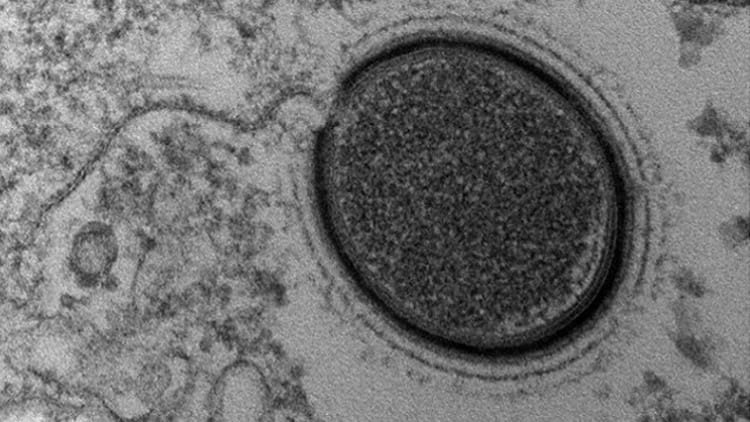

Un equipo internacional de científicos ha encontrado una nueva vía para impedir que el virus de la inmunodeficiencia humana (VIH), causante del síndrome de inmunodeficiencia adquirida...

¿Y si todo lo que supiéramos acerca del VIH fuera sólo una gota de agua en medio del océano? Una nueva investigación publicada en Cell Reports muestra un mecanismo tan...